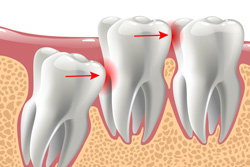

Although our ancient ancestors often needed this third set of molars to replace lost teeth early on and to help with chewing tougher foods, modern diets and smaller mouths make wisdom teeth unnecessary. In fact, because of better oral hygiene and shrinking oral cavity sizes, they can even put the rest of your smile at a much higher risk of damage, infection, alignment shifting, and pain. When your mouth is unable to make space for them, removing wisdom teeth before they start to cause harm preserves your teeth for the rest of your adult life.

Most of the time, wisdom teeth are still submerged in the gums, which means the extraction requires very minor surgery. After your mouth has been completely numbed with a local anesthetic, a small incision gives us access to these teeth, and if they are simple, we can manage to remove them with little effort and close the gum tissue with stitches. If you have a more complex case, we will kindly refer you to a trusted local expert in these types of procedures, practically guaranteeing the success of your extraction.